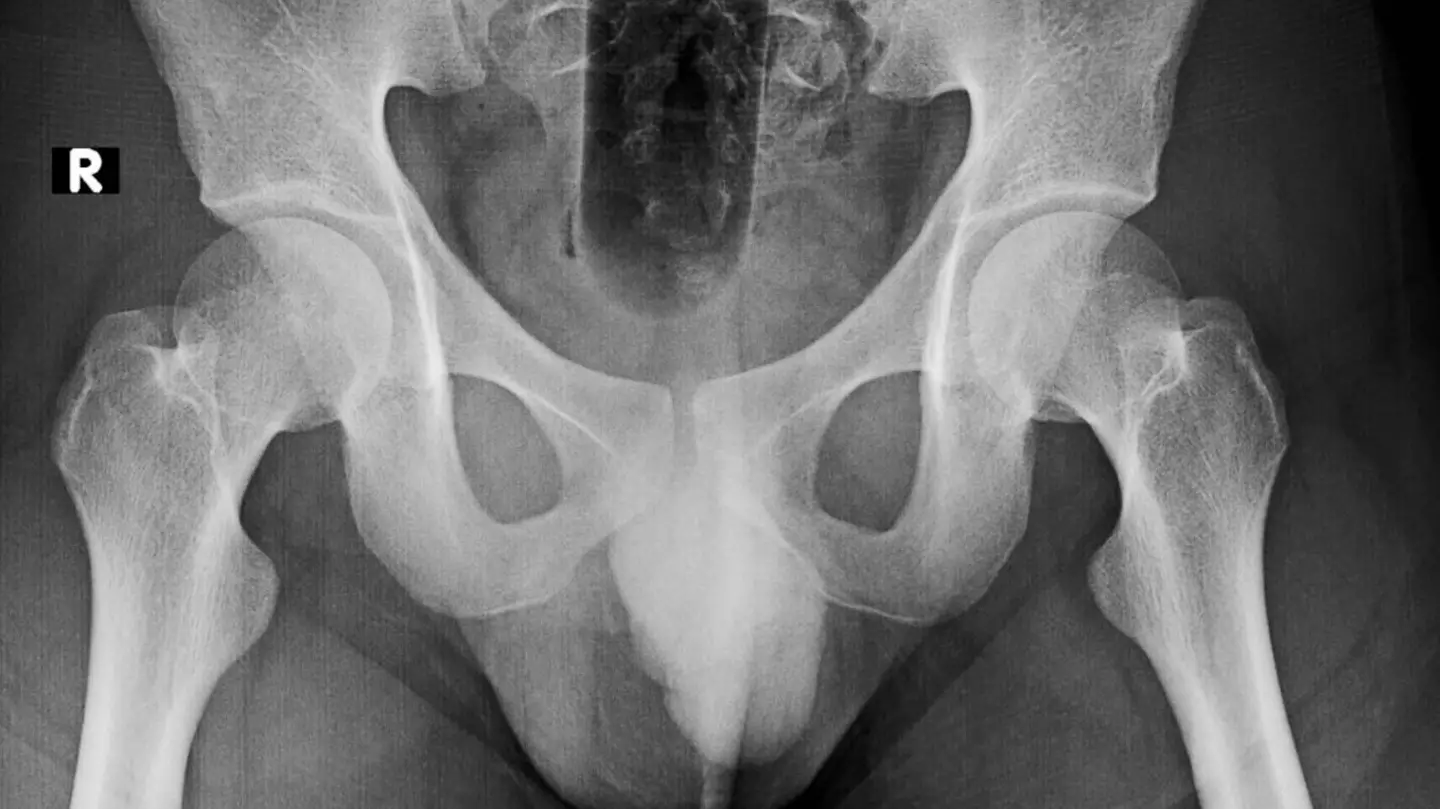

It was only after undergoing surgery that staff found a 16x4cm WWI shell dating back over 100 years to 1918 inside him, La Dépêche reports.